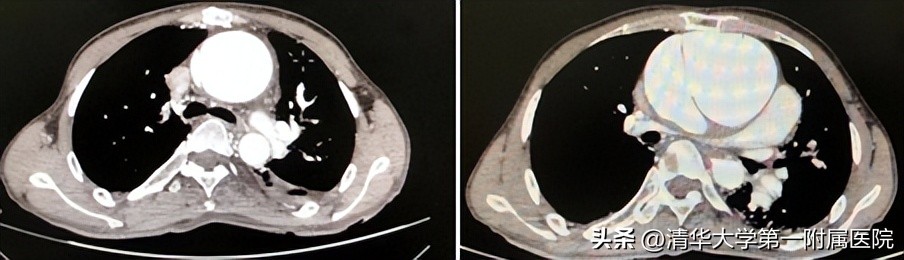

张明奎院长了解到小段的既往病史以及目前胸痛症状,及时开具了心脏彩超、胸片等检查,结果出来后令所有人大吃一惊。心脏超声提示主动脉窦部及升主动脉瘤样扩张,升主动脉夹层或假性动脉瘤可能性大,建议进一步检查。张明奎院长敏锐地觉察到,这是一位病情十分危重、紧急的患者,他立即联系心脏中心三病房将患者收入院。急诊完善全主动脉CTA检查,证实了张明奎的诊断:主动脉夹层,升主动脉瘤样扩张。

患者入院后张明奎院长十分关注患者病情,立即进行病例讨论。由于患者自幼患有先天性心脏病,且接受过心脏手术,因此患者情况不同于普通的主动脉夹层的患者,对于这类二次手术的主动脉夹层患者来说,手术难度和风险极大。患者的心脏与周围血管、肺脏、胸骨粘连紧密,CTA提示主动脉夹层紧贴胸骨,单纯打开胸骨的过程,会随时有夹层破裂导致大出血的凶险。

在详尽地讨论后,张明奎院长带领心脏中心团队为小段进行了第二次“续命”的手术治疗。术中出现了尤为惊心动魄的瞬间:由于是二次手术,粘连严重,术中发现患者的升主动脉与胸骨紧密粘连, 主动脉瘤样扩张,直径达到15cm(正常升主动脉直径不超过4cm),像一个吹弹可破的水球一样,随时都有爆裂风险!